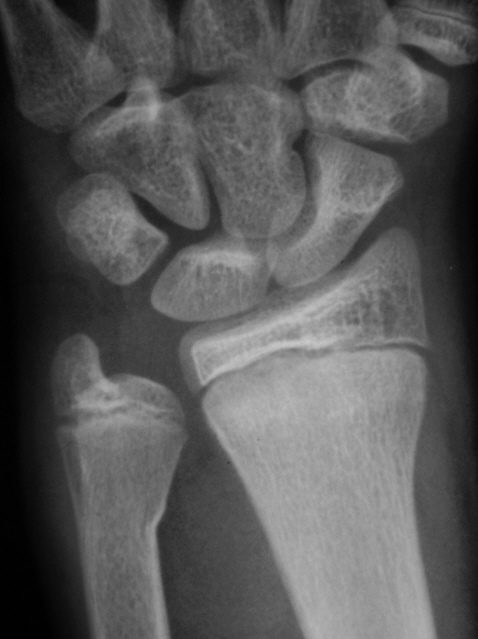

Случай № 4.

4. Остеоэпифизеолиз луча  в н/3 и перелом локтевой в н/3.

А я считаю,что в №4 поднадкостничный перелом обеих костей предплечья в н/3, в боковой проекции виден перелом лучевой кости.

Случай №4: Остеоэпифизеолиз дистальный лучевой кости, со смещением к тылу до 10мм. Перелом шейки локтевой кости, поднадкостничный, с незначительным смещением.